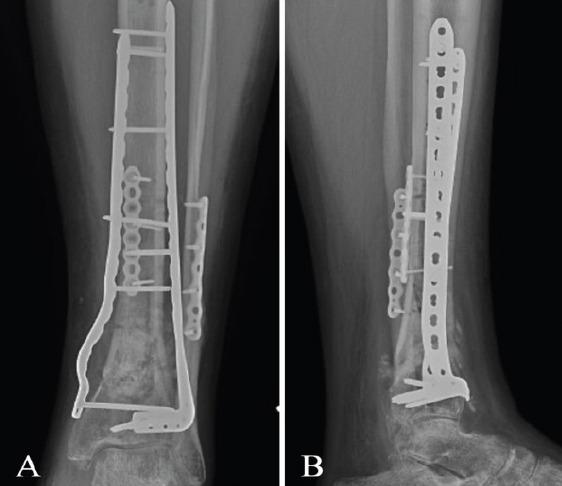

A 47-year-old male presented with an open pilon fracture of the left ankle after falling off a 6-foot ladder. At his 4-month post-operative follow-up, the patient attempted to ambulate without his cam boot for the 1st time, causing acute displacement of his poorly healed tibia fracture. A non-union laboratory workup demonstrated elevated inflammatory markers indicative of septic non-union; however, the patient also tested positive for severe acute respiratory syndrome coronavirus 2 at this time. Because of this, antibiotic treatment was not initiated due to suspicion of a cytokine storm. One month later, the patient's inflammatory markers had decreased and he underwent revision surgery.

一名47岁男性从6英尺高的梯子上跌落,导致左踝开放性Pilon骨折。术后4个月随访时,患者首次尝试在未穿戴膝关节固定支具的情况下行走,导致愈合不佳的胫骨骨折急性移位。骨折不愈合的实验室检查显示炎症标志物升高,提示感染性骨折不愈合;然而,此时该患者的严重急性呼吸综合征冠状病毒2检测也呈阳性。因此,由于怀疑存在细胞因子风暴,未开始使用抗生素治疗。1个月后,患者的炎症标志物有所下降,随后接受了翻修手术。